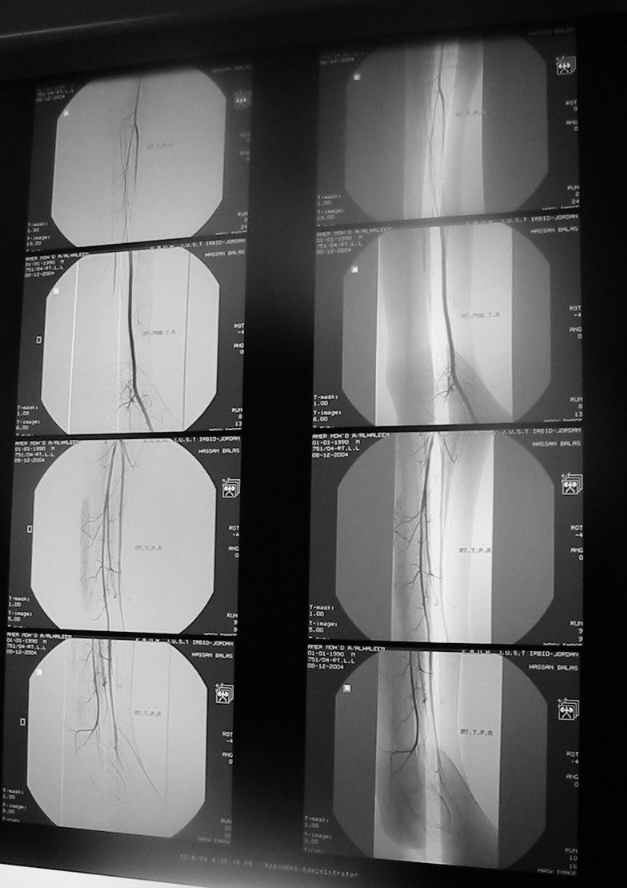

Судя по представленным фото и Рг граммам, у 13 летнего ребенка врождённая гемимелия большеберцовой кости, таранно-пяточный синостоз Из-за отставания в росте большеберцовой кости (остутствует дистальный эпифиз с зоной роста) произошла компенсаторная гиперофия малоберцовой кости, на которую приходится основная нагрузка (спонтанная тибиализация малоберцовой кости). Как результат дисбаланса осевого роста вторично возникла эквино-варусная деформация стопы. Продолжающийся рост ребёнка (до естественного закрытия зон роста) будет приводить к усугублению деформации по приведенным выше причинам.

Своё наблюдение только одно (ребёнка наблюдали и продолжаем наблюдать с рождения) и дважды оперировали: 1 этап выполнили проксимальный тиб/фиб фьюжн вторым этапом медиализация малоберцовой кости с таранно- малоберцовым синостозом и ещё предстоят этапы по удлинению тибиализированной малоберцовой кости.

В вашем случае я бы избрал следующую тактику:

Поднадкостничную остеотомию большеберцовой кости в средней трети с формированием синостоза с малоберцовой ( активно растущей) костью и второй уровень в области дистального тиб/фиб синдесмоза- достигается баланс роста( средне-медиальный и латеральный отделы) в области измененного голеностопного сустава. Коррекция эквино-варусной деформации стопы в аппарате после чрезкожной сегментарной тенотомии ахилова сухожилия. Дело

кропотливое и длительное.

Как резервный вариант может быть рассмотрена ампутация в верхней трети голени с изготовлением функционального протеза, если родители ребенка не настроены на длительную коррекцию и многоэтапную хирургию, родственники должны понимать, что абсолютного функционального результата даже после этапных операций достичь будет невозможно (аномальный голеностопный сустав, таранно-пяточный синостоз).